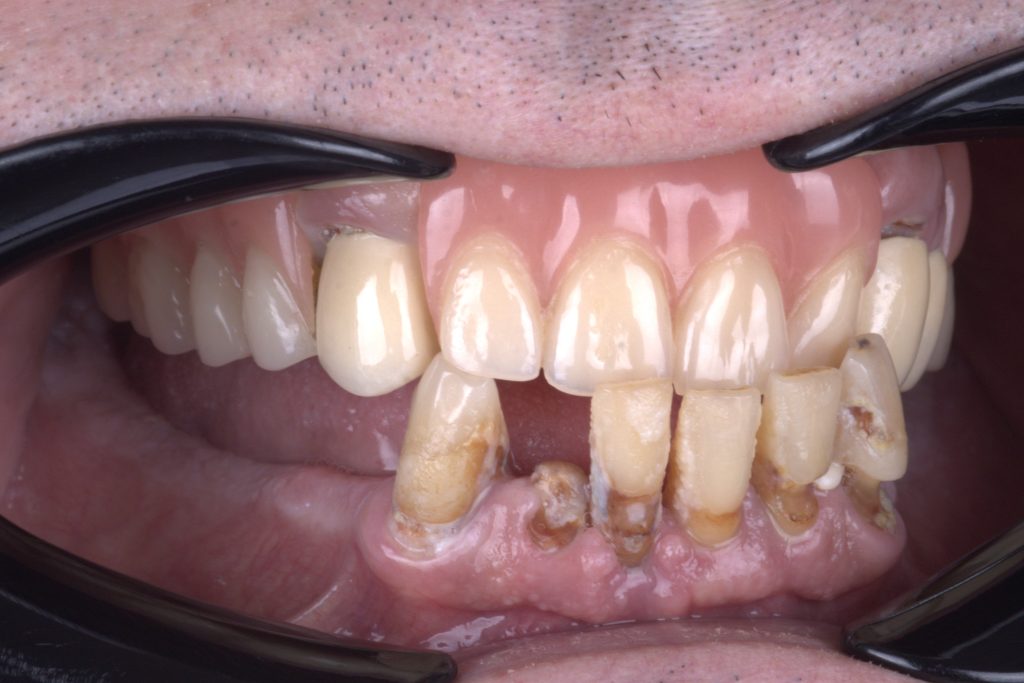

ПОЧЕТНО СТАЊЕ

Делимична протеза на горњој вилици и каријес корена и пародонтална болест на доњој вилици.

Делимична протеза на горњој вилици, недостајућа дентиција, каријес корена и пародонтална болест на доњој вилици

Терминална дентиција.

Преостали зуби нису довољни за будућу рестаурацију.